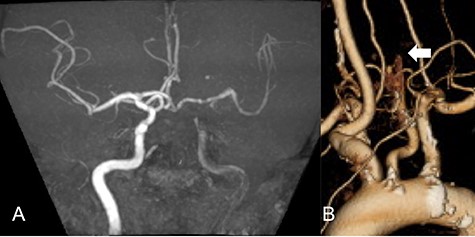

A 69-year-old male visited the emergency department presenting right hemiplegia and total aphasia. The final safety confirmation was 9-h ago. The National Institutes of Health Stroke Scale score was 10. Diffusion weighted imaging (DWI) in magnetic resonance imaging showed high signal intensity in the left frontal lobe and basal ganglia. Magnetic resonance angiography (MRA) revealed a left CCA occlusion with collateral flow via anterior communicating and posterior communicating arteries (Fig. 1A). Computed tomography angiography (CTA) scanning also showed left CCA occlusion without aortic dissection (Fig. 1B). We could not find any clinically significant problem of the patients except atrial fibrillation detected on an electrical cardiogram. We initiated anticoagulant treatment based on finding chronic atrial fibrillation.

MRA demonstrated left CCA occlusion with collateral flow via anterior and posterior communicating arteries (A). CTA showed left CCA occlusion without aortic dissection (white arrow: B).